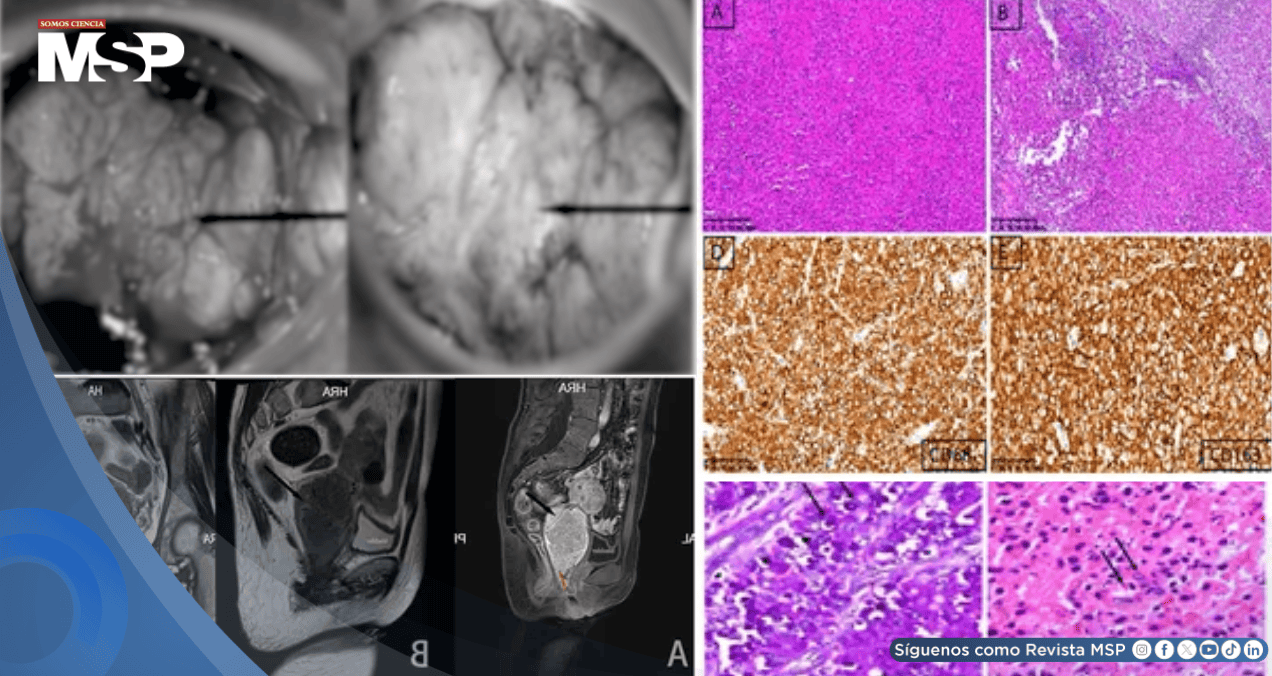

Inicialmente, la presentación clínica sugería un tumor maligno cervical. Sin embargo, el estudio histopatológico reveló hallazgos característicos de malacoplaquia, una enfermedad inflamatoria rara.

El microscopio mostró una gran cantidad de macrófagos agregados con los característicos cuerpos de Michaelis-Gutmann, considerados patognomónicos de esta entidad. El cultivo bacteriano identificó Escherichia coli, lo que apoyó el diagnóstico definitivo.